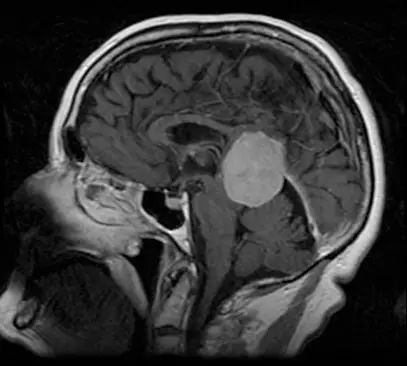

虽然脑膜瘤常为偶然发现,但大多数可通过临床症状鉴别。脑膜瘤起源于蛛网膜,而蛛网膜覆盖了整个神经轴。因此,尽管大多数病变于颅内发现,病变也可发生在整个神经系统。实际上,90%脑膜瘤位于幕上,其余发生在后颅窝或脊髓。脑膜瘤有几种常见的发生部位(尽管仅发生于脑室系统很少见),临床表现可随特定部位而变化。下图为增强MRI扫描T1加权像,显示松果体区脑膜瘤,可以看到附着于小脑幕的硬脑膜。